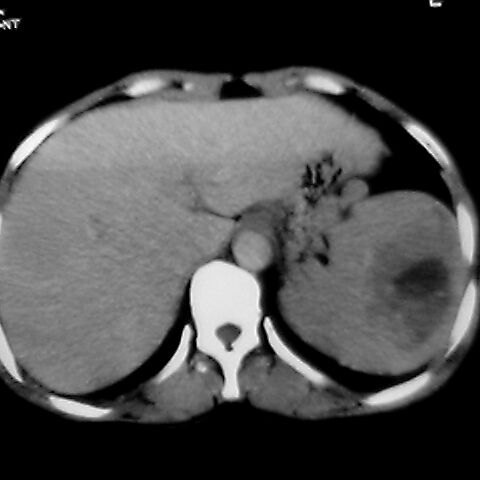

女 48岁 食道癌术前体检发现脾占位。

脾胀内部巨大低密度肿块,边界清或不清,中心坏死,轻度增强,内见散在钙化,结合食道癌病史多考虑:转移癌.

1肝右下叶小囊肿2右肾上极囊肿或错构瘤3脾脏不典型血管瘤可能性大.

脾脏低密度灶伴钙化,增强化明显,中心见液化坏死灶,强化延时明显。考虑血管瘤。转移瘤待排。